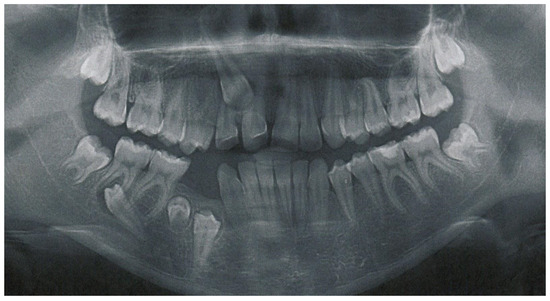

2. Case Report